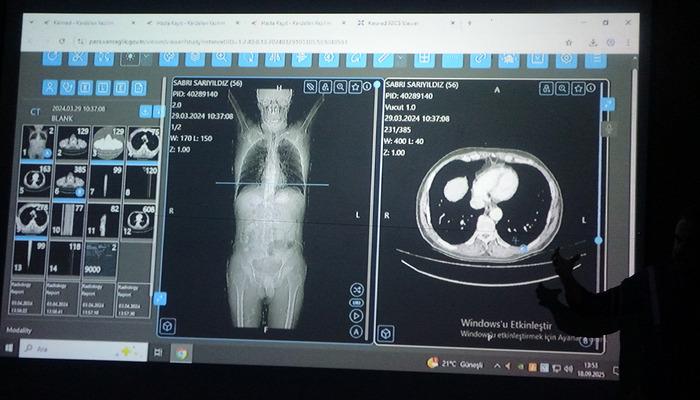

Dünyaya örnek oldu! Türkiye’de bir ilk: Kanser tedavisinde yapay zeka kullanıldı